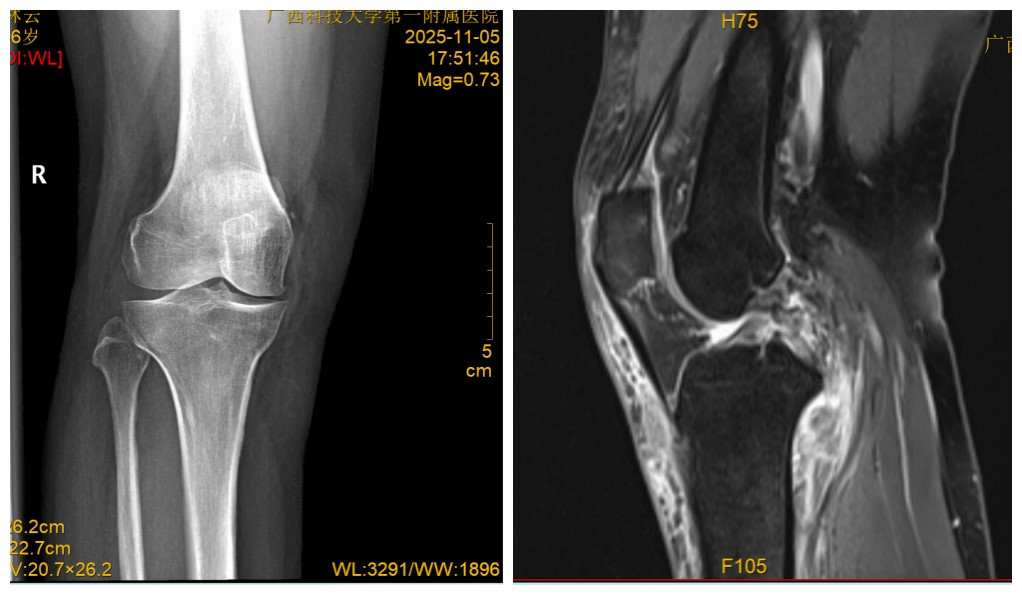

近日陆女士遭遇“刹车门”事件:坐在后排由于车辆急刹车导致双侧膝关节疼痛、活动受限,急诊就诊X线及CT检查结果显示双膝关节未见明显骨折,MRI检查结果令人揪心:双膝关节后交叉韧带断裂、半月板撕裂。随着时间的推移,双膝关节越来越肿,无法正常行走,随即来我院骨科住院,入院后完善相关术前检查。

图1 X线 图2 MRI